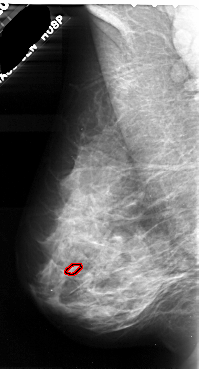

A_1047_1.LEFT_CC

LEFT_CC LINES 5116 PIXELS_PER_LINE 2851 BITS_PER_PIXEL 16 RESOLUTION 42 OVERLAY

FILE: A_1047_1.LEFT_CC.OVERLAY

TOTAL_ABNORMALITIES 1

ABNORMALITY 1

LESION_TYPE CALCIFICATION TYPE PLEOMORPHIC DISTRIBUTION CLUSTERED

ASSESSMENT 4

SUBTLETY 2

PATHOLOGY MALIGNANT

TOTAL_OUTLINES 1

BOUNDARY